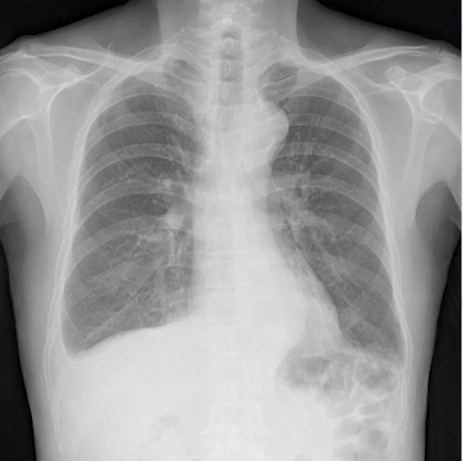

無症状なら肺癌を疑い、有症状なら肺炎や胸膜炎を疑うレントゲン写真(X-p):CPA dull(肋横隔膜角の鈍化)のレントゲン

同じレントゲン写真でも患者さんを診察し、症状を聴取しないと鑑別できないレントゲン写真もあります(CPA dull)。

CPA dullとは胸水が溜まっている場合に肋骨と横隔膜のなめらかな弓状のカーブが鈍くなり、鋭さが失われて丸く見えることです。

正常時のレントゲン:胸部X線の正面像で、横隔膜の尖った部分(肋横隔膜角、CP angle)は鋭い切れ込みのように見える。

CPA dullの場合:胸水が貯留すると、通常鋭角である肋横隔膜角が丸みを帯び、鈍角(flat)に見えます。

本症例のレントゲン所見としては、右CPA dull、右肺は毛髪線も見えます。これは右胸水が示唆されます。

無症状なら肺癌を疑い、発熱あれば肺炎や胸膜炎疑います。